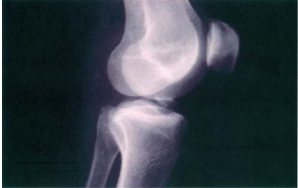

35 45 歲朱女士因膝關節酸痛來就醫,X 光檢查發現如圖所示,則關於其診斷與處置,下列敘述何者正確?

(A)浮髕試驗陽性 (B)應加強股四頭肌之訓練 (C)抽屜試驗陽性 (D)此為髕骨脫位